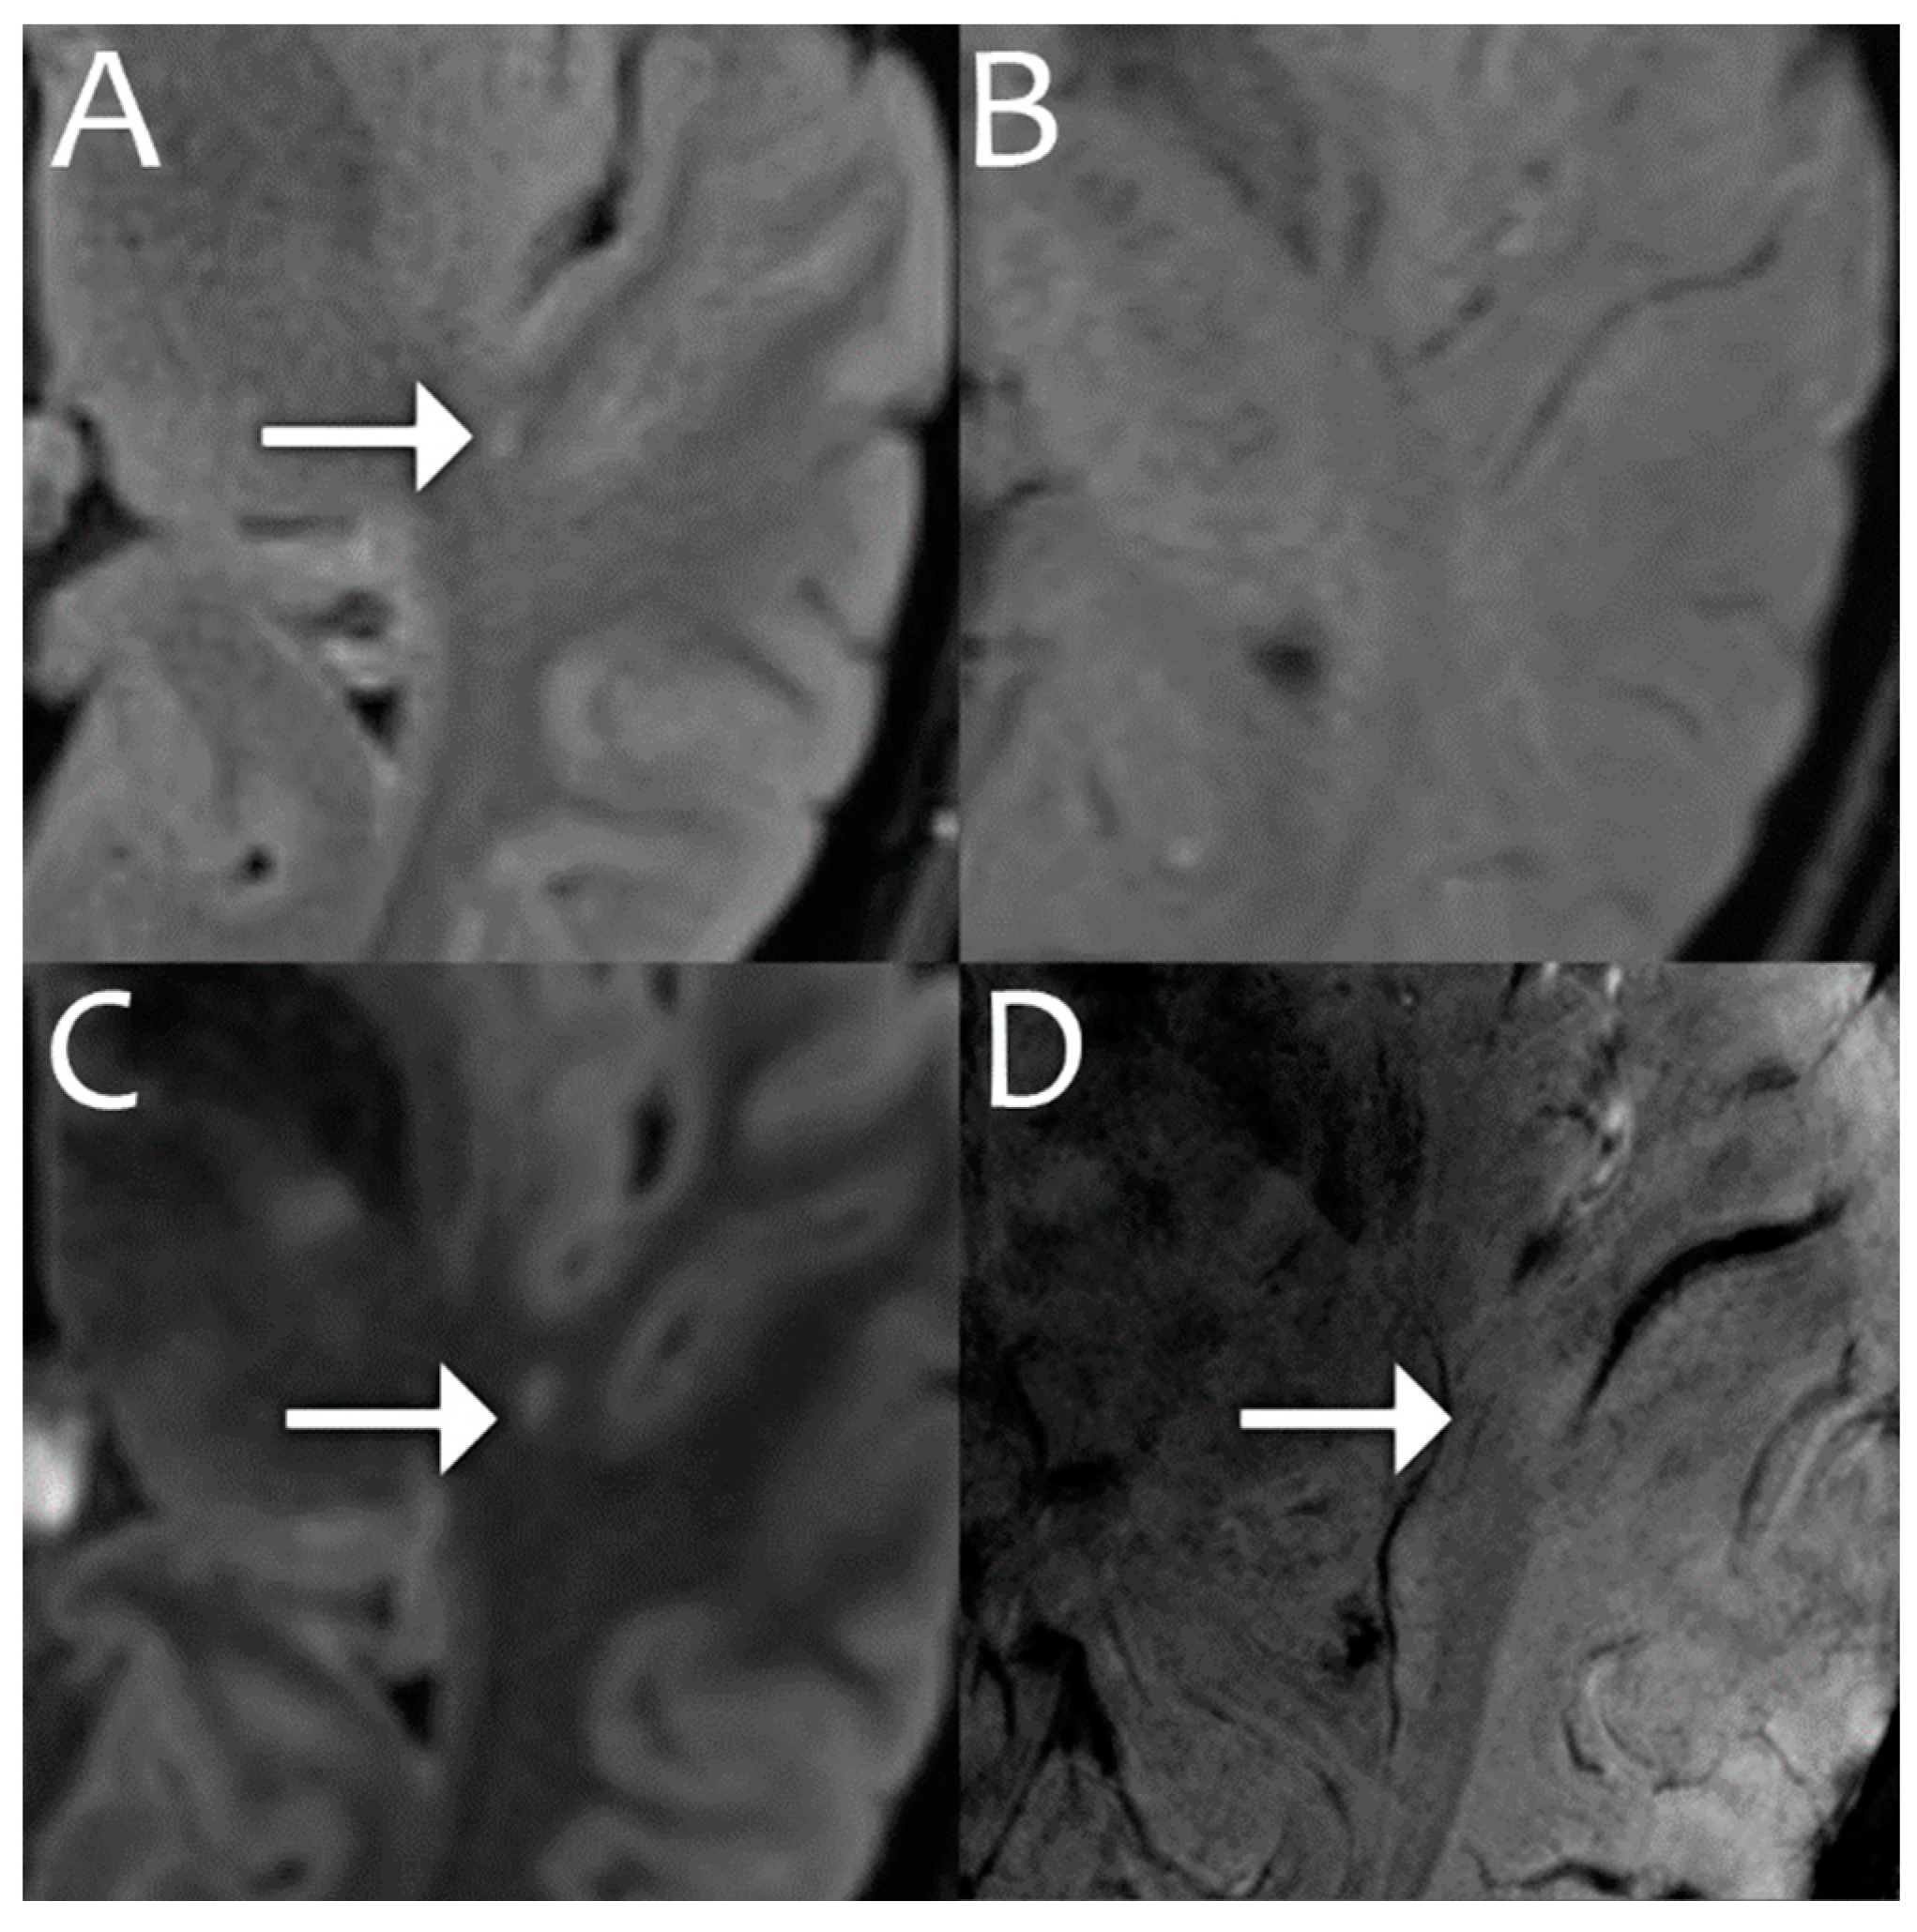

- Veersema, T.J.; Ferrier, C.H.; van Eijsden, P.; Gosselaar, P.H.; Aronica, E.; Visser, F.; Zwanenburg, J.M.; de Kort, G.A.P.; Hendrikse, J.; Luijten, P.R.; et al. Seven tesla MRI improves detection of focal cortical dysplasia in patients with refractory focal epilepsy. Epilepsia Open 2017, 2, 162–171. [Google Scholar] [CrossRef]

- Okromelidze, L.; Patel, V.; Singh, R.B.; Chiriboga, A.S.L.; Tao, S.; Zhou, X.; Straub, S.; Westerhold, E.M.; Gupta, V.; Agarwal, A.K.; et al. Central Vein Sign in Multiple Sclerosis: A Comparison Study of the Diagnostic Performance of 3T versus 7T MRI. Am. J. Neuroradiol. 2023, 45, 76–81. [Google Scholar] [CrossRef]

- Clarke, M.A.; Cheek, R.; Kazimuddin, H.F.; Hernandez, B.; Clarke, R.; McKnight, C.D.; Derwenskus, J.; Eaton, J.; Irlmeier, R.; Ye, F.; et al. Paramagnetic rim lesions and the central vein sign: Characterizing multiple sclerosis imaging markers. J. Neuroimaging 2023, 34, 86–94. [Google Scholar] [CrossRef]

- Wermer, M.J.; van Walderveen, M.A.; Garpebring, A.; van Osch, M.J.; Versluis, M.J. 7 Tesla MRA for the differentiation between intracranial aneurysms and infundibula. Magn. Reson. Imaging 2017, 37, 16–20. [Google Scholar] [CrossRef] [PubMed]